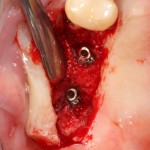

во время операции (плюс снимок по завершении):

Вернемся к нашему клиническому случаю. Мы уже поставили импланты с расчетом на будущую высоту альвеолярного гребня и положение будущих зубов:

И, если в предыдущей части мы рассматривали ситуацию, когда принимающее ложе имеет относительно простой рельеф, и у нас не возникло сложностей с адаптацией аутоблока, то в случае, рассматриваемом сегодня, нормальная и точная адаптация крупного костного фрагмента, практически, невозможна. Именно поэтому мы решили использовать направленную костную регенерацию (НКР), поскольку с адаптацией тестообразного по консистенции графта проблем, обычно, никогда не бывает. Как, например, в этом случае: